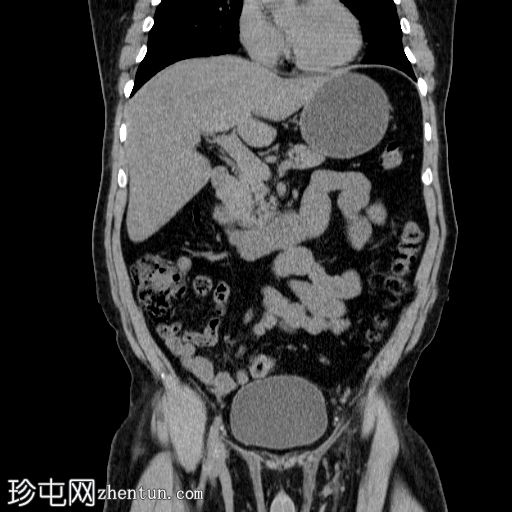

冠状位

平扫

左肾盂及肾盏系统内可见多发边界清晰的高密度结石,最大直径约2 cm,平均CT值约418 HU。

结石呈典型的球形形态。

左肾盏系统及肾盂轻度扩张至肾盂输尿管连接处,提示肾盂输尿管连接处梗阻,但未见输尿管扩张或肾周脂肪浸润。